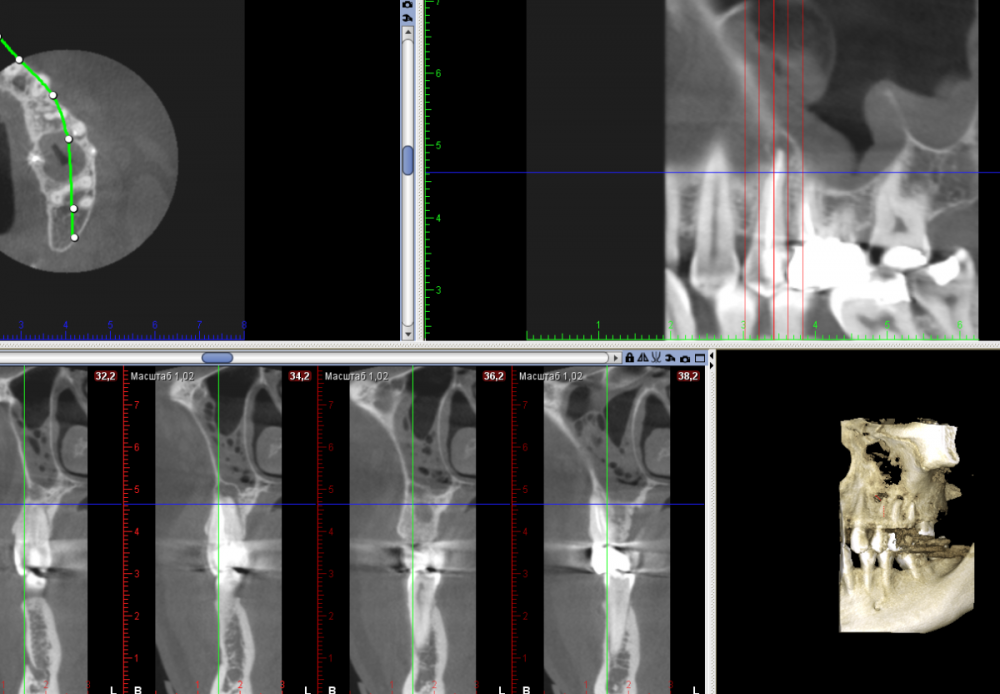

Большой Зеленый Опубликовано 10 декабря, 2021 Поделиться Опубликовано 10 декабря, 2021 Гайморит непроходящий 2 года, неоднократное обращение к ЛОРам . После эндо 25 зуба через 5 месяцев.. 3 2 Ссылка на комментарий

Большой Зеленый Опубликовано 11 декабря, 2021 Автор Поделиться Опубликовано 11 декабря, 2021 Сделан был только один сегмент , мне кажется все видно. Это действительно аппарат Планмека . Ссылка на комментарий